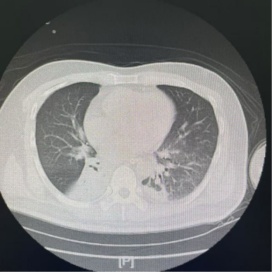

主管医生多次尝试堵管(封闭气切套管口,观察能否自主呼吸),但每次都以失败告终。原因很简单:只要一堵管,张大爷就憋得满脸通红,血氧饱和度急剧下降。胸部CT显示,他的右下肺呈现不张状态,大量的痰液像“淤泥”一样堵塞了深部的支气管。

术后复查胸部CT显示:原本不张的右下肺已基本复张。医生再次尝试堵管,张大爷呼吸平稳,没有丝毫憋闷感。